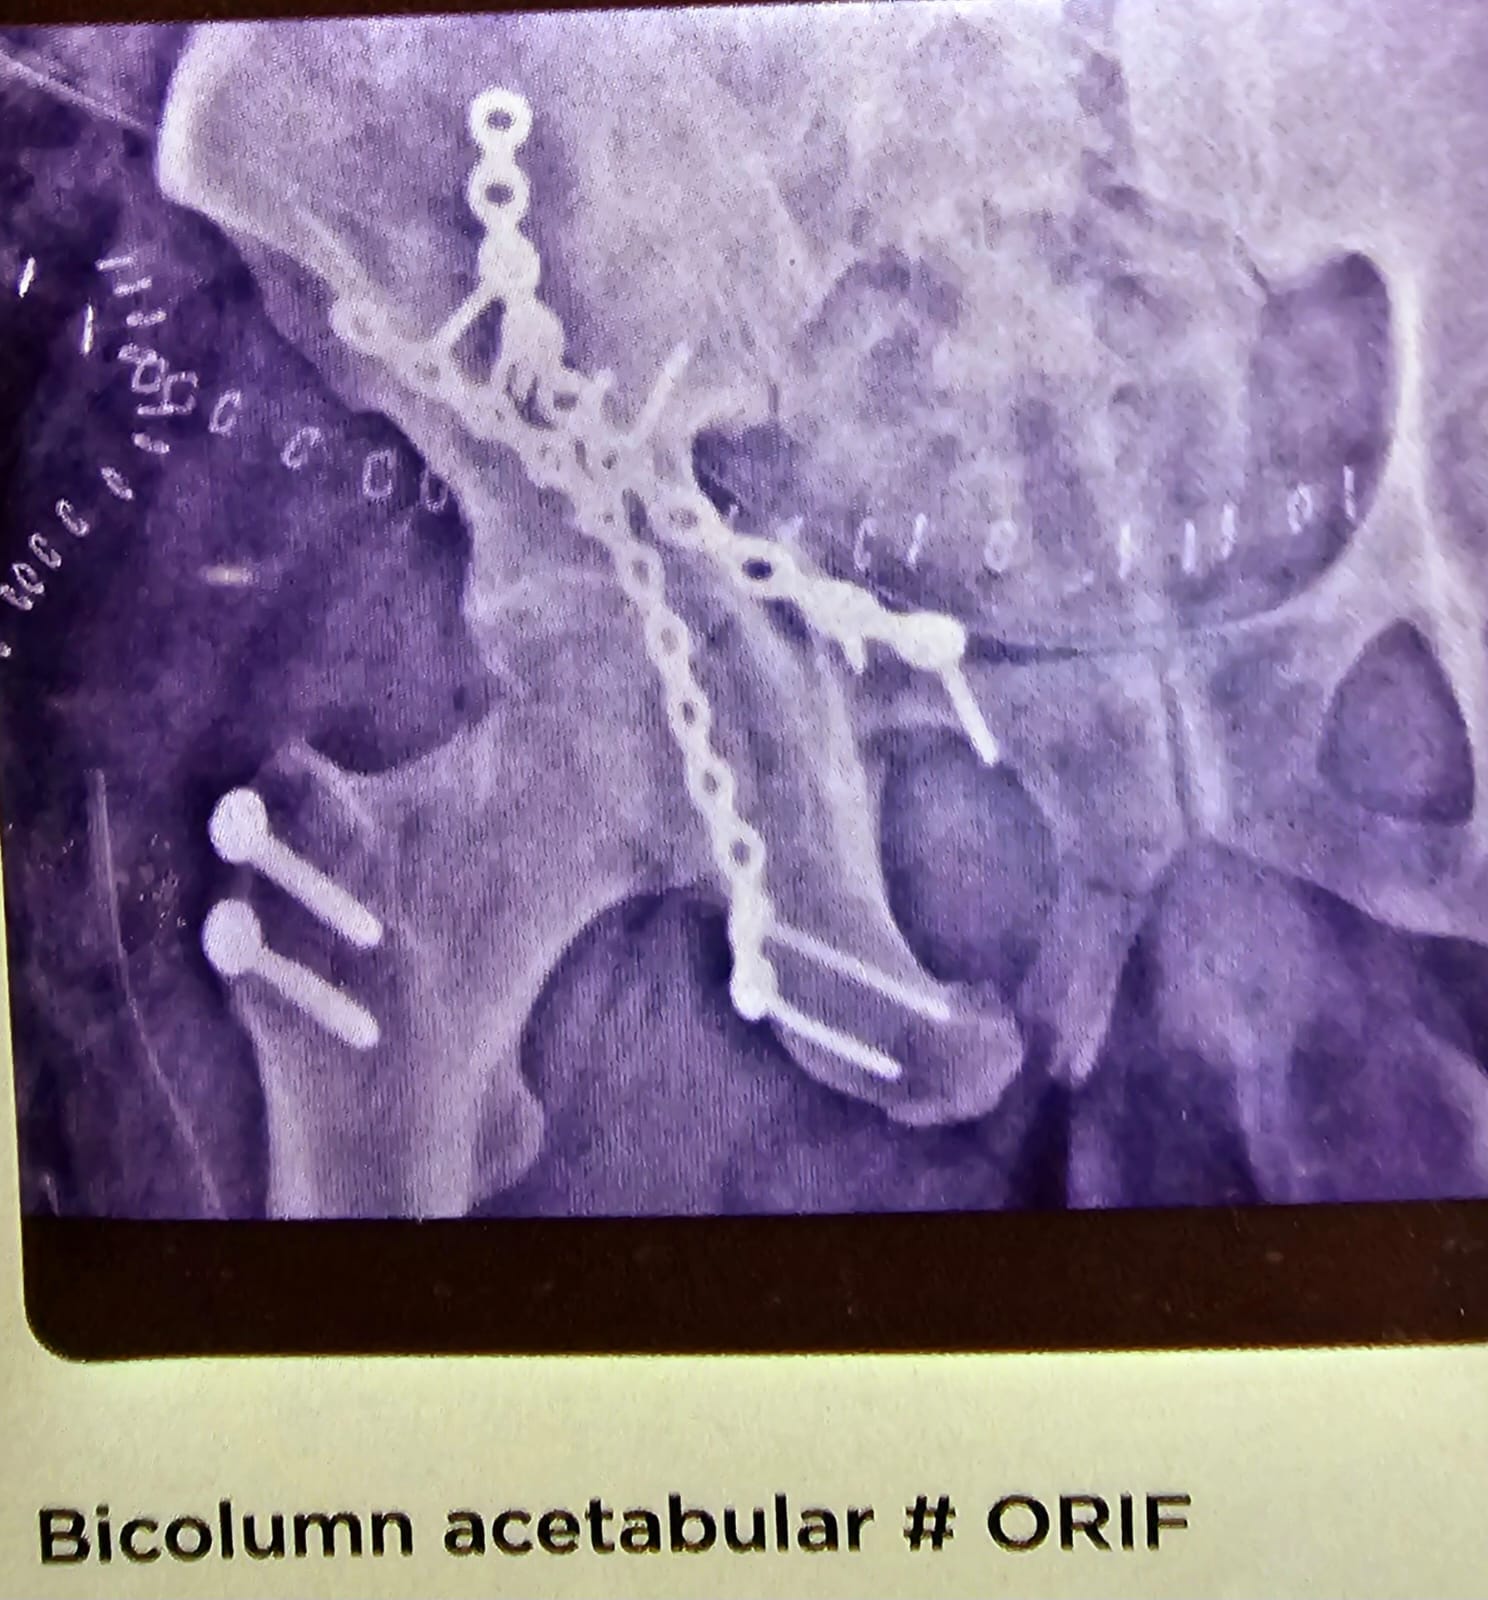

Bicolumn Acetabular #ORIF

This is a interesting case of bi column acetabular fracture that was approached using the GANZ approach. Where in the GT was osteotomised and re fixed with the help of two screws and the bi column was plated in two different directions. One into skil tuberosity and the other one up to the pubic ramus. The patient did very well.